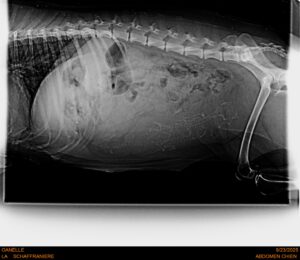

OANELLE devrait mettre bas aux alentours du 5 ou 6 octobre, avec 3 chiots.

RADIO DE OANELLE